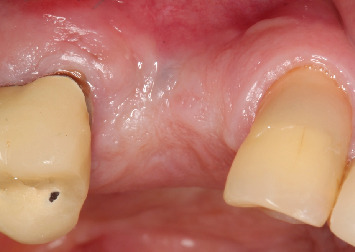

背景:缺牙是一个世界性的问题,影响患者的社会和功能。种植体康复是金标准治疗;然而,可能需要先进行骨重建。杠铃技术是一种引导骨再生技术,推荐用于各种形态的缺陷,允许垂直和水平单向或双向再生,即在颊侧和腭侧/舌侧。本文的目的是报告一例在种植体康复之前的后上颌骨重建,其中杠铃技术与窦提升一起进行。方法:本研究报告了一名77岁男性患者,其右侧第一和第二双尖缺失,并有种植体丢失的历史。最初的CT扫描显示水平和垂直牙槽萎缩,使种植体无法放置。采用鼻窦提升术进行垂直恢复,Barbell技术进行水平再生,使用胶原膜覆盖的异种骨。6个月后,新的CT扫描显示骨容量足够,并根据数字计划引导放置两个植入物。结果:植骨前后的CT扫描显示水平骨增重70%,垂直骨增重33%。重建手术6个月后,植入牙种植体,45天后安装单个冠。在24个月的随访中,未观察到与种植体或假体相关的并发症。结论:在这个临床病例中,这是文献中第一次,这些技术的结合使缺损再生,随后将植入物放置在理想位置并进行假肢康复。

Background: Dental absences are a worldwide issue, affecting patients both socially and functionally. Implant rehabilitation is the gold standard treatment; however, prior bone reconstructions may be necessary. The Barbell Technique is a guided bone regeneration technique recommended for defects of various morphologies, allowing for vertical and horizontal unidirectional or bidirectional regeneration, that is, both on the buccal and palatal/lingual sides. The objective of this paper is to report a case of bone reconstruction in the posterior maxilla prior to implant rehabilitation, where the Barbell Technique was performed together with a sinus lift. Methods: This study consists of a case report of a 77-year-old male patient with the absence of first and second right bicuspids and a history of implant losses in the area. The initial CT scan showed horizontal and vertical alveolar atrophy, making implant placement impossible. Regeneration was performed using a sinus lift for vertical recovery and the Barbell Technique for horizontal regeneration, using xenogeneic bone covered by a collagen membrane. After 6 months, a new CT scan suggested sufficient bone volume, and two implants were guidedly placed based on digital planning. Results: Comparison of CT scans before and after the grafts showed a horizontal bone gain of 70% and a vertical gain of 33%. Six months after the reconstructive surgery, dental implants were placed, followed by the installation of individual crowns after 45 days. At the 24-month follow-up, no complications related to the implants or prostheses were observed. Conclusion: In this clinical case, for the first time in the literature, the association of the techniques allowed the regeneration of the defect, with the subsequent placement of implants in the ideal position and prosthetic rehabilitation.